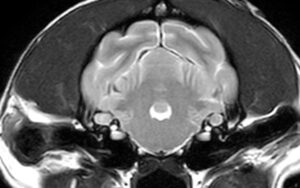

CTは骨構造を詳細に見ることができるが、脳や内耳は骨構造に囲まれているため、内部の構造の評価は困難。

脳や内耳の評価にはMRI検査が推奨される。